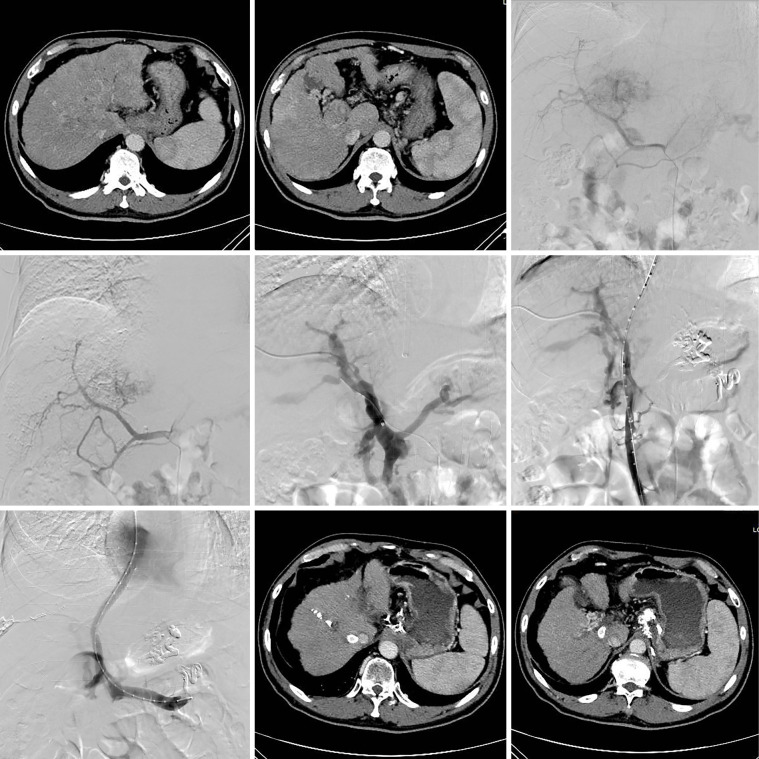

Methods: In this retrospective study, 21 patients with HCC complicated with PHT who were admitted to The Second Hospital of Nanjing between June 2018 and June 2023 were included. TIPS was performed, and liver and kidney function, blood routine, and biochemical indicators such as ammonia were examined preoperatively, at 1 week postoperatively, and at 1 month postoperatively. To determine the improvements in stent blood flow, ascites, and esophageal and gastric varices, ultrasound and/or enhanced computed tomography were performed. Treatment was evaluated based on the Modified Solid Tumor Efficacy Evaluation Criteria. Parameters such as portal vein pressure and portal blood flow before and after TIPS were analyzed using paired-sample t-tests.

Results: Postoperatively, the direct pressure of the portal vein of patients decreased significantly from 28.33±7.15 to 19.27±3.10 mmHg (P<0.05). The amount of ascites also significantly decreased, whereas esophageal and gastric varicose veins significantly improved. Meanwhile, no significant differences were observed in liver or kidney function indicators, including bilirubin, transaminase, and creatinine, from the preoperative to the postoperative period.

Conclusions: TIPS can effectively improve the various symptoms of PHT without increasing the incidence of liver function damage or other complications in patients with HCC complicated with PHT.